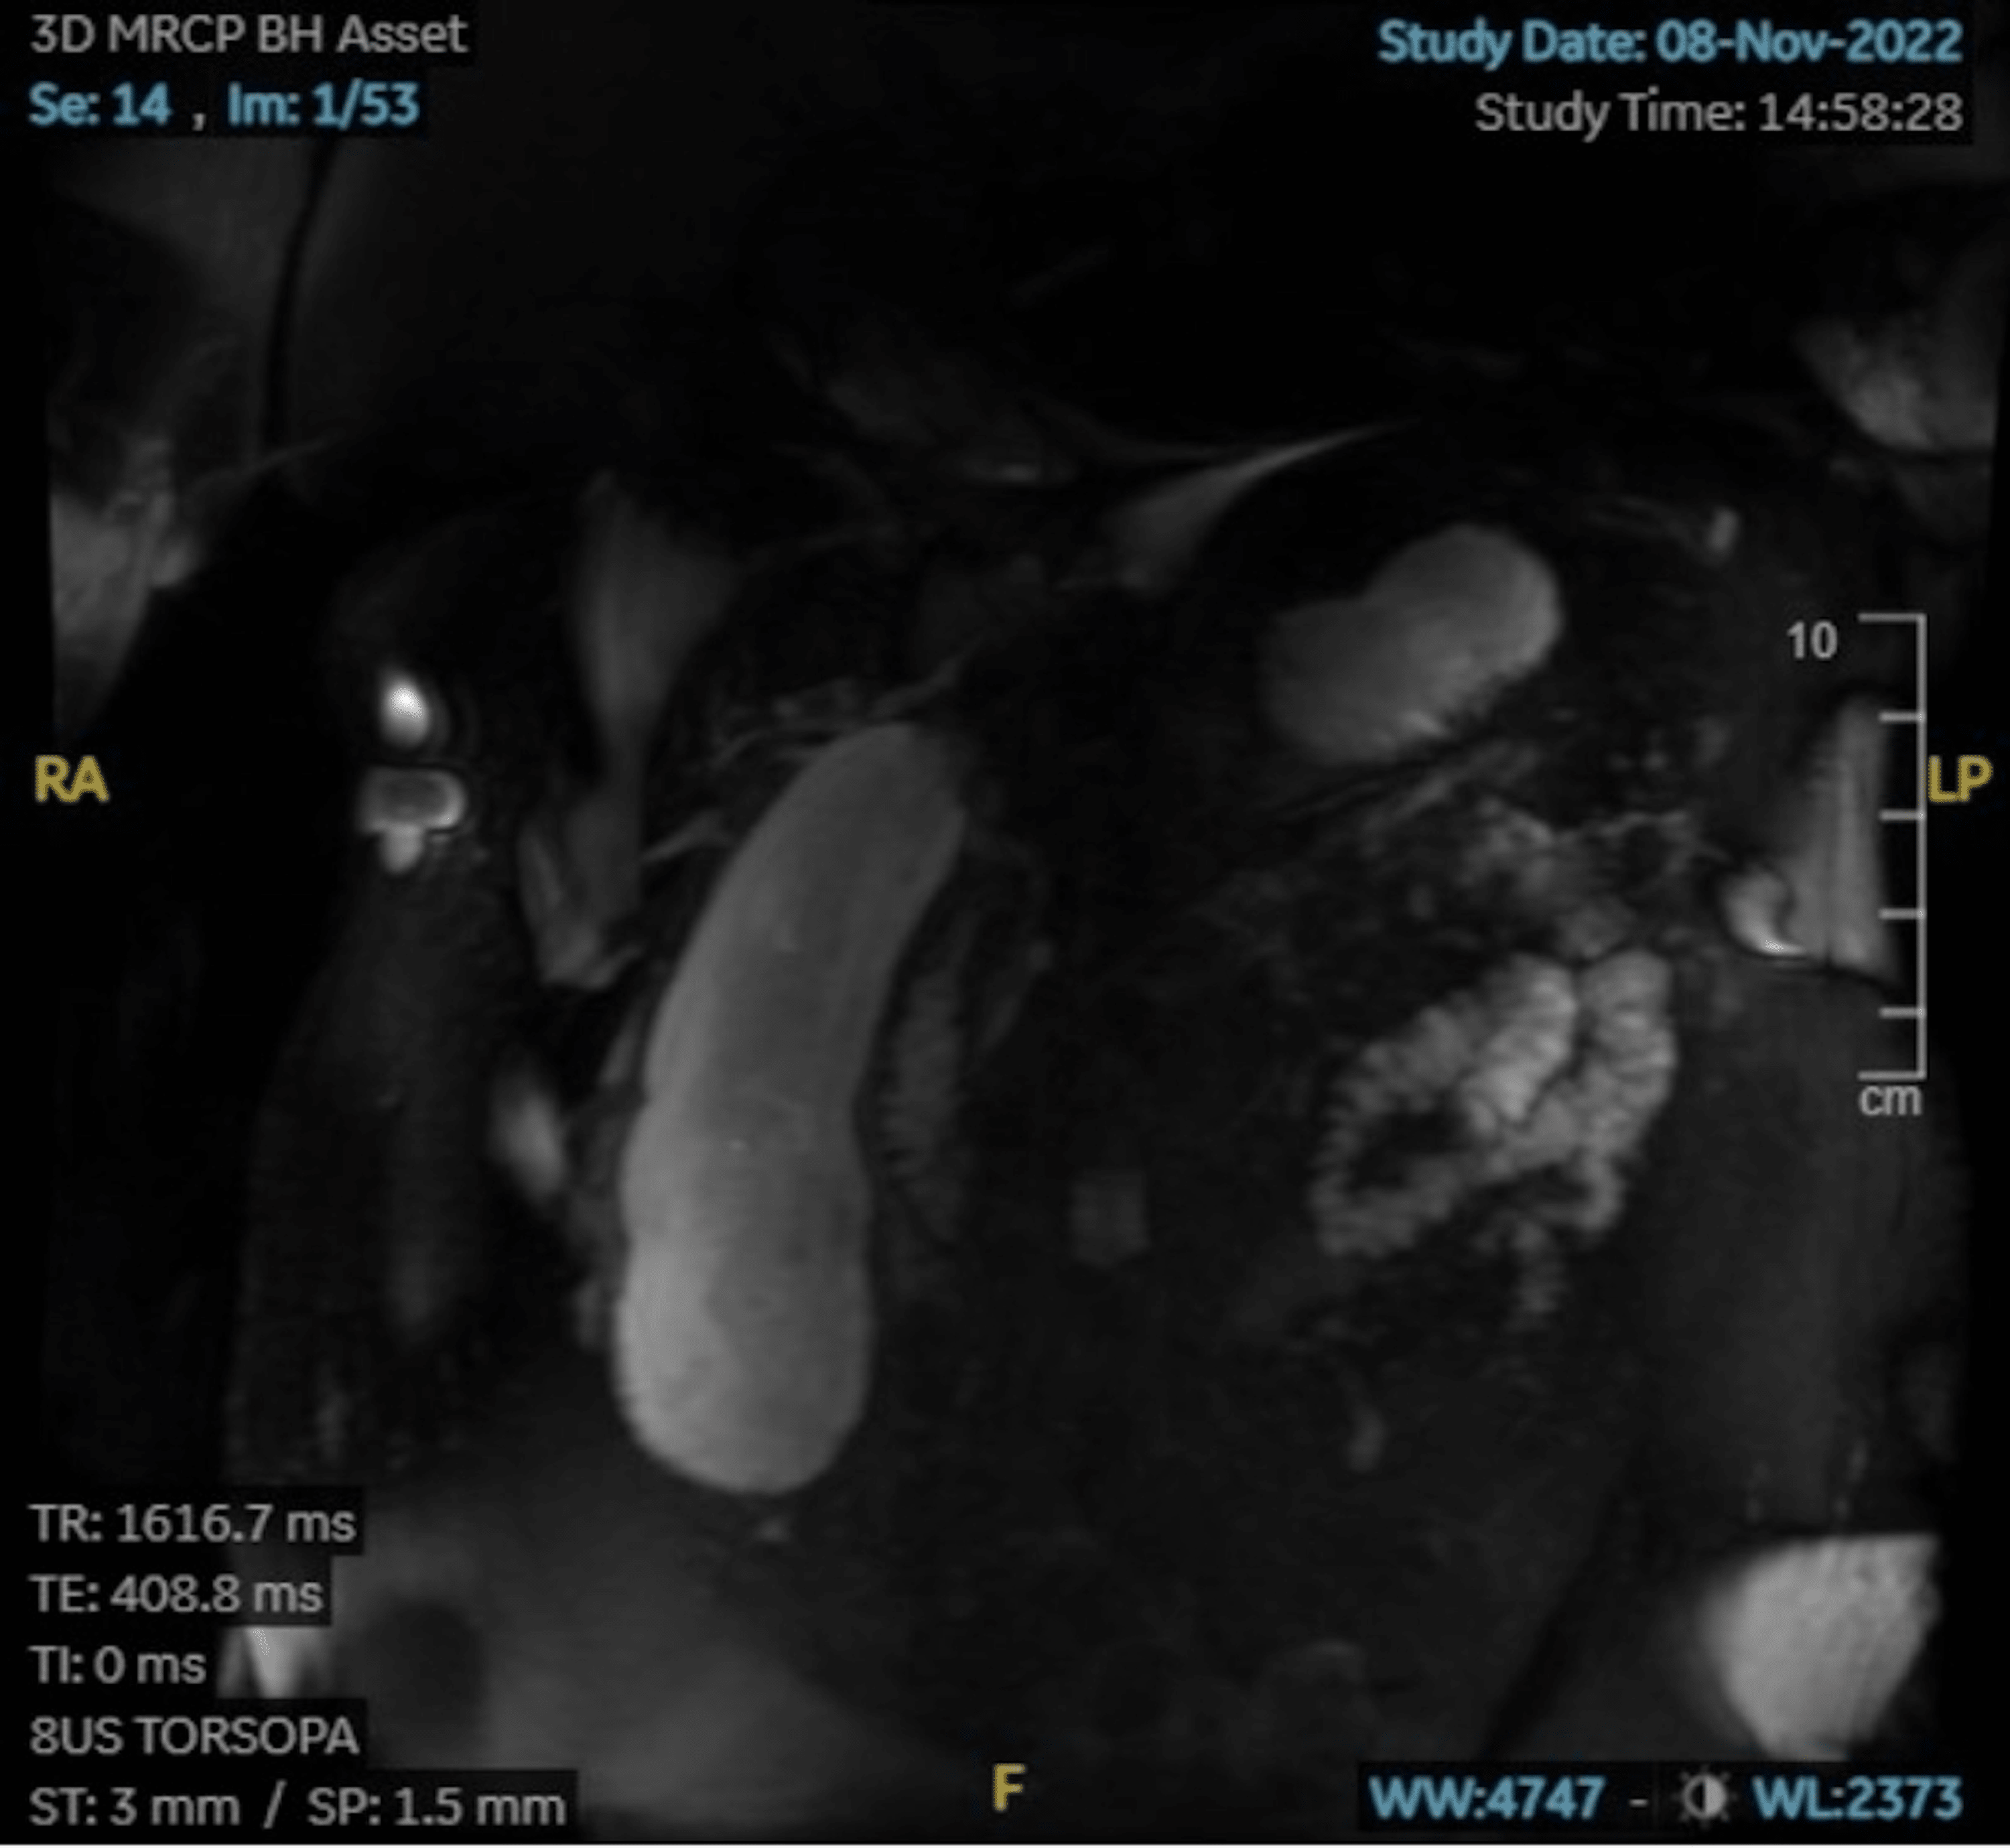

Cholecystitis Undergraduate Diagnostic Imaging Fundamentals Liver Enzymes Cholecystitis liver function tests (lfts) use for common bile duct stone (cbds) prediction in acute cholecystitis (ac) patients is challenging, especially in patients. — liver enzymes may also be elevated. — acute cholecystitis (ac), generally associated with the presence of gallstones, is a relatively frequent disease. If there is a high bilirubin level above 2, then consider a. Liver Enzymes Cholecystitis.